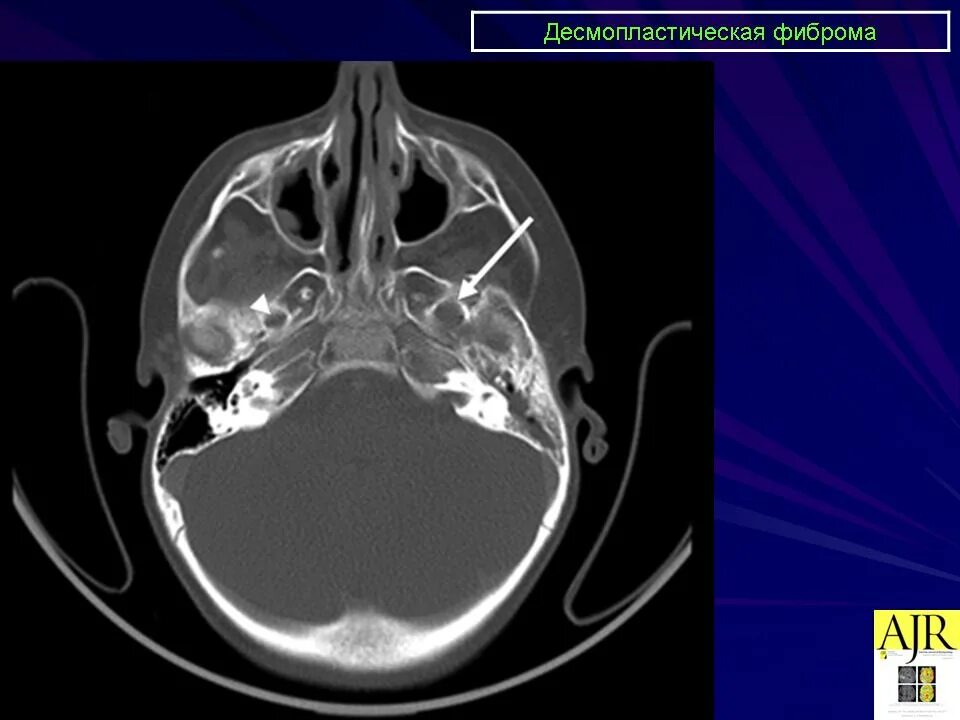

Фиброма кт